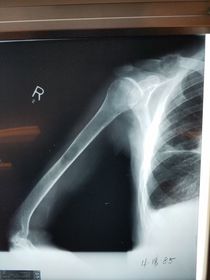

Which projection/position is this? Transthoracic Shoulder ___________________ ribs are blurred out from orthostatic breathing

Transthoracic Lateral Humerus *trauma only 40 SID 70-85 kVp 14x17 IR grid CR @ mid-diaphysis through the thorax expose during orthostatic respiration (gentle, short, shallow breaths) *if pt. in too much pain to drop shoulder and elevate the opposite shoulder over the head, angle CR 10-15 degrees cephalad

Transthoracic Lateral Shoulder *trauma 40 SID 70-85 kVp 10x12 IR grid CR directed through thorax to the level of the affected surgical neck *expose during orthostatic breathing